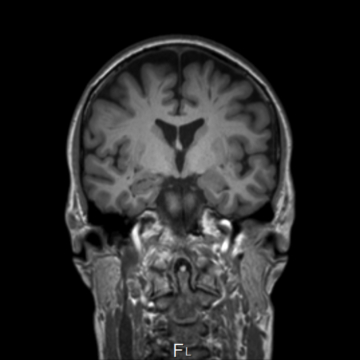

Paediatric MRI: High-Resolution in vivo 3T Methods

View full preprint on https://doi.org/10.1101/2025.10.30.685686

HumanBrainAtlas: an in vivo MRI dataset for detailed segmentations

View full preprint on https://doi.org/10.1101/2022.10.16.511844